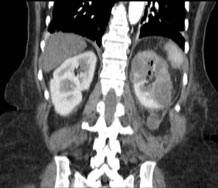

Przypadek ephysematosus pyelonephritis u pacjentki z cukrzycą

A case of emphysematous pyelonephritis in diabetic patient

Surgery

Krajewski W., Krajewska M., Dołowy Ł.

Emphysematous pyelonephri􀆟s (EPN) is an acute complication of urinary tract infection with bacteria that produce gas. The mortality rate in this condition, according to some authors, can be as high as 80%. The most common pathogen causing EPN is Escherichia coli. Therapy is based on empirical administration of antibiotics and surgical treatment.